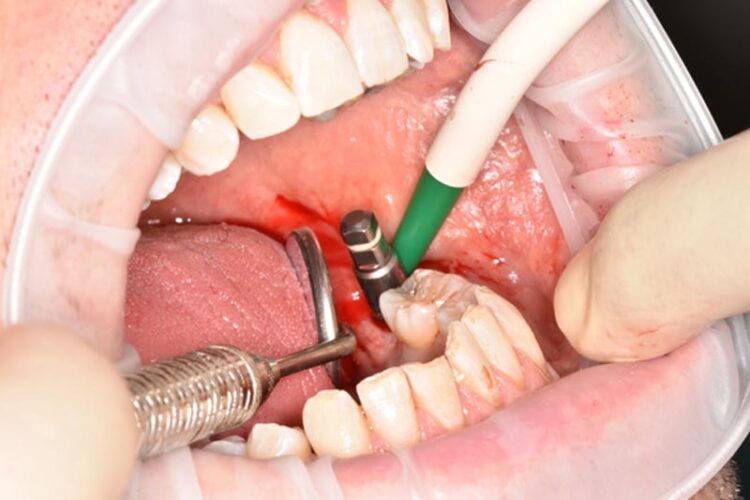

3-D radiographic examination showed sufficient bone available for the placement of a 5.8mm x 9mm BioHorizons Camlog tapered tissue level implant. Surgical placement of this implant involved a two-sided flap and there was no need for hard or soft tissue augmentation. The implant was placed with excellent primary stability and therefore a single-staged approach was followed with a healing abutment being placed at implant placement.

The implant was then left to heal and integrate for three months. No temporary prosthesis was required during this phase.